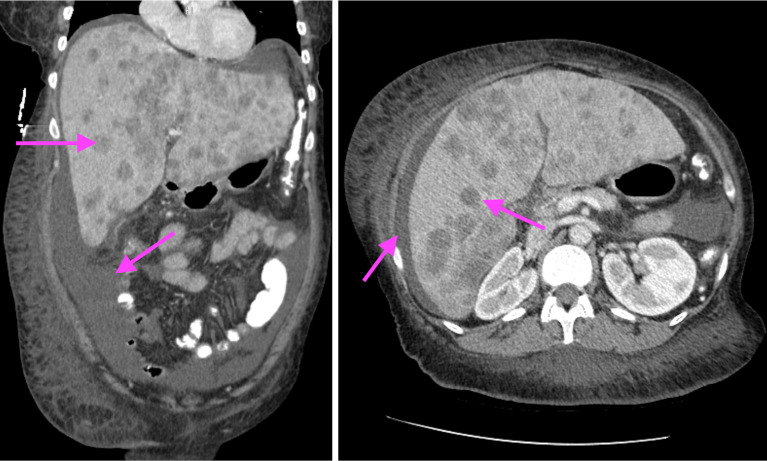

Case description: We present a rare case of HHM secondary to cholangiocarcinoma. This case presents a rare case of HHM due to cholangiocarcinoma with an atypical presentation in a 55-year-old female. This patient presented with abdominal swelling and severe hypercalcemia prompting evaluation for a possible gastrointestinal source and was found to have HHM due to cholangiocarcinoma. She was treated for her hypercalcemia medically, however due to the extent of her disease she was unable to undergo surgery. Chemotherapy was not considered during her initial presentation as she originally had a malignancy of unknown primary. Ultimately, shortly after her initial presentation, the patient passed at another hospitalization 36 days after her initial presentation.